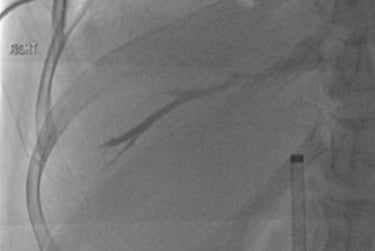

Venografía por punción transhepática eco-guiada

Punción y colocación de guía transhepática hacia la unión cavoatrial inferior